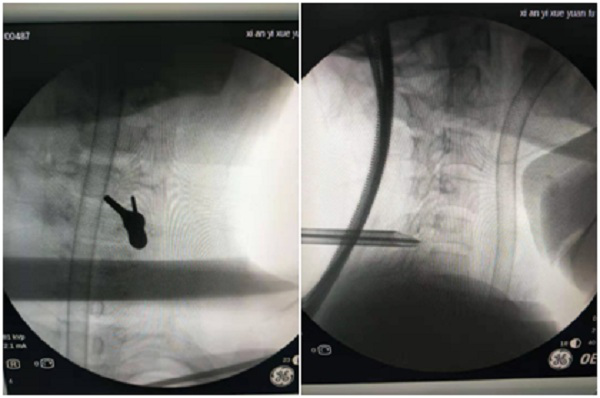

11月16日,在王礼副主任医师、任文静主管医师、手术麻醉科等医护人员的共同努力下手术顺利完成。术后病人的疼痛、麻木缓解消失,行动自如,术后5天康复出院。

术中C型臂引导下椎间孔镜置入顺利

术中显露神经根、神经根腋下突出髓核

术中取出两块髓核组织